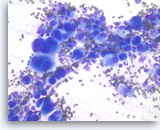

Plasma cell neoplasm,

Pancreas FNA, Direct Smear.

The aspirates show dispersed single cells with a prominent plasmacytoid appearance. The tumor cells vary slightly in size. Rare mitoses are seen.

20X

Plasma cell neoplasm,

Pancreas FNA, Direct Smear.

The aspirates show dispersed single cells with a prominent plasmacytoid appearance. The tumor cells vary slightly in size. Rare mitoses are seen.

20X